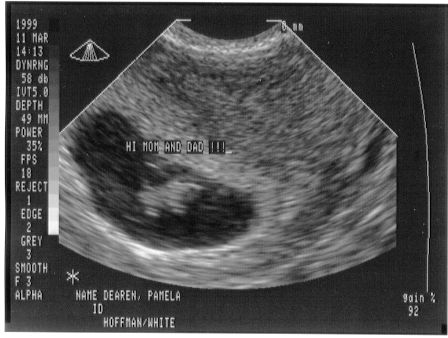

This is me at 7 weeks and 2 days. Mom and Dad got to see my heart beating for the first time.